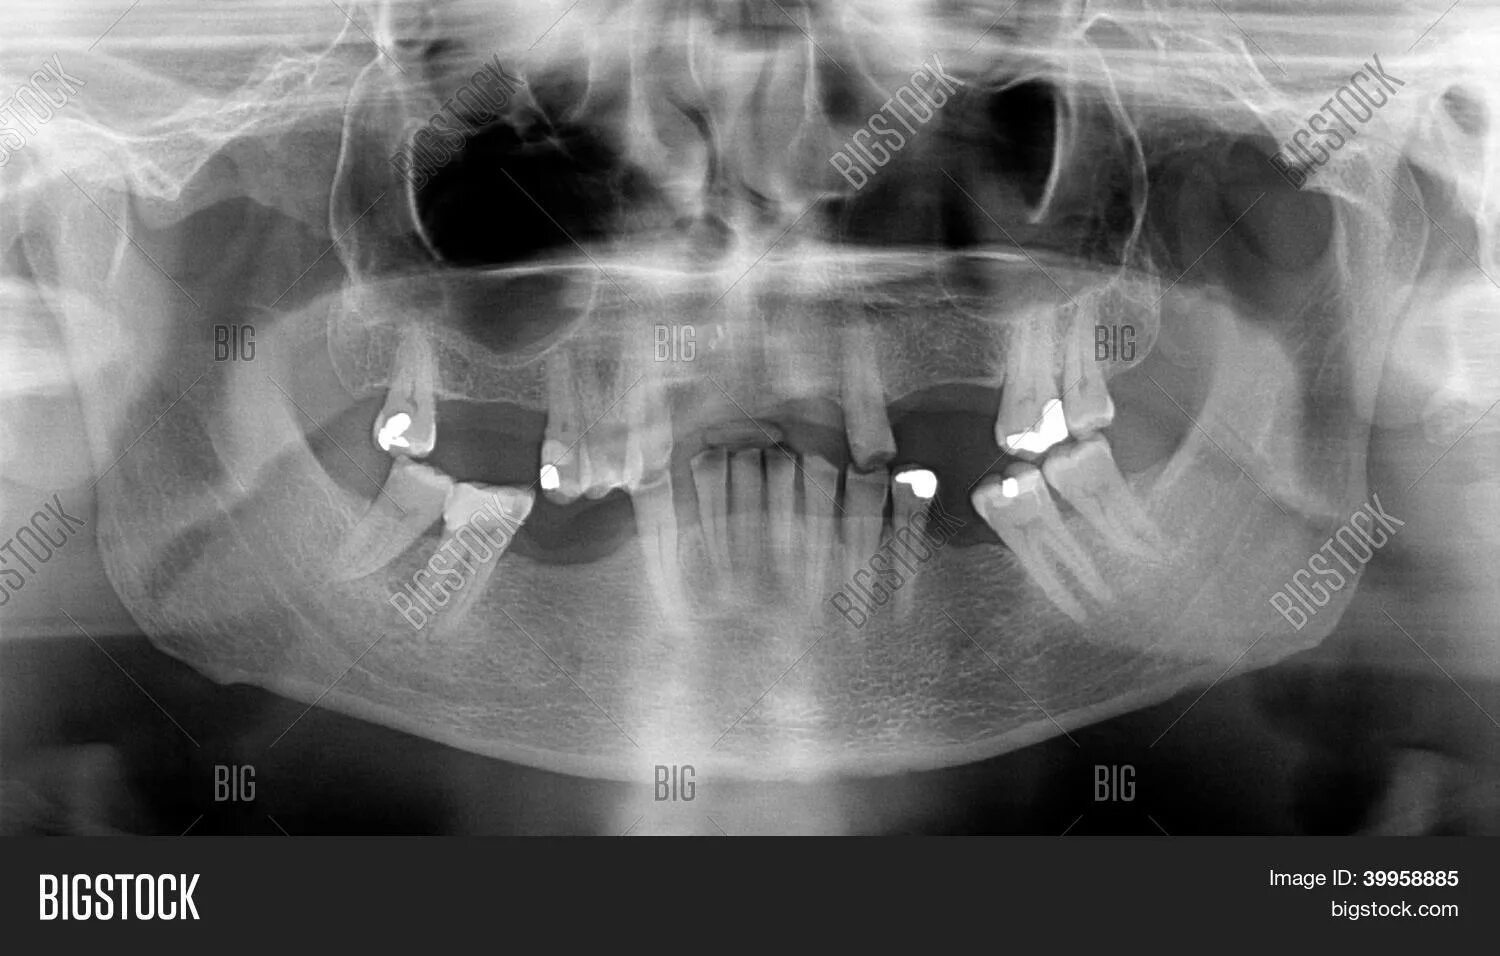

Снимок ротовой полости